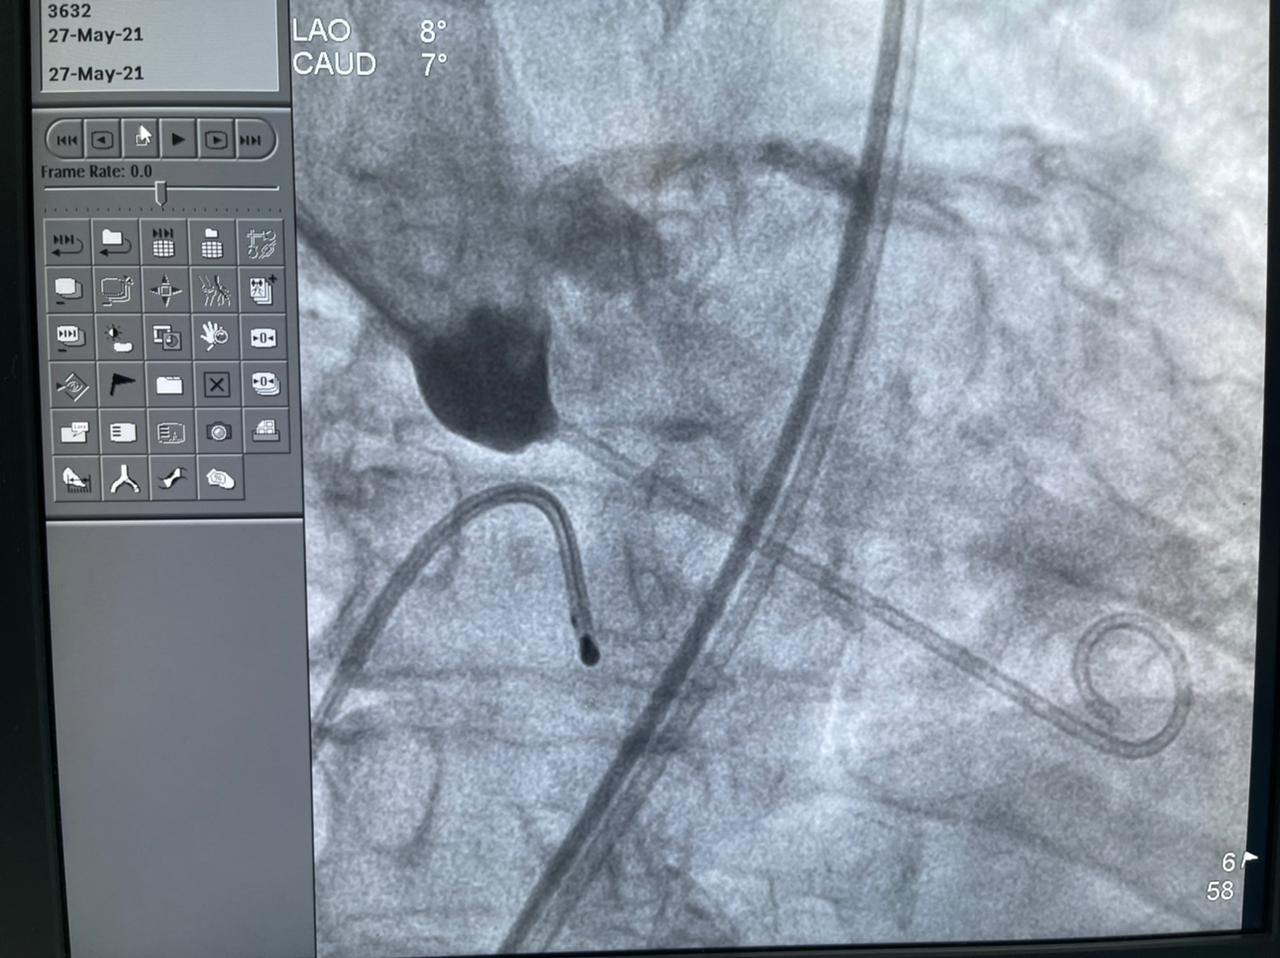

وأضافت الهيئة أن الحالة الثانية هي عملية زراعة الصمام الأورطي لمسنة تبلغ من العمر 78 عامًا، كانت تعاني من ضيق شديد بالصمام الأورطي، وتمت العملية بنجاح بعد أن كانت تعاني من تعب شديد وضيق بالتنفس وآلام بالصدر ونوبات إغماء، وتم إقرار علاج المريضة بعملية زراعة الصمام نظرًا لتقدم عمرها والضعف العام لحالتها الصحية، وتم إجراء العملية بتقنية التافي العالمية التي يتم بها تغيير الصمام الأورطي عن طريق القسطرة.

وتابعت الهيئة أنه قام بإجراء العمليات للمرضى الثلاثة في يوم واحد، فريق من أمهر الأطباء الأخصائيين والاستشاريين في علاج أمراض القلب والقساطر القلبية، يضم، الدكتور طارق رشيد أستاذ القلب والقسطرة وخبير حالات الانسداد المزمن للشرايين التاجية ورئيس قسم القسطرة القلبية بمستشفى النصر التخصصي، والدكتور ياسر صادق استشاري القلب وخبير القسطرة القلبية، الدكتور أمير البسطويسي استشاري جراحة القلب والصدر، الدكتور أحمد شبل استشاري القلب والقساطر التداخلية، الدكتور محمد علم الدين استشاري القلب والقسطرة العلاجية، الدكتور محمد لبيب استشاري جراحة الأوعية الدموية، وإخصائي علاج أمراض القلب والأوعية الدموية الدكتور معتز سلامة و الدكتور محمد عطا، أخصائي علاج أمراض القلب والقسطرة العلاجية الدكتور مصطفى رفعت، الدكتور أحمد عبد الرؤوف أخصائي التخدير بالمستشفى.